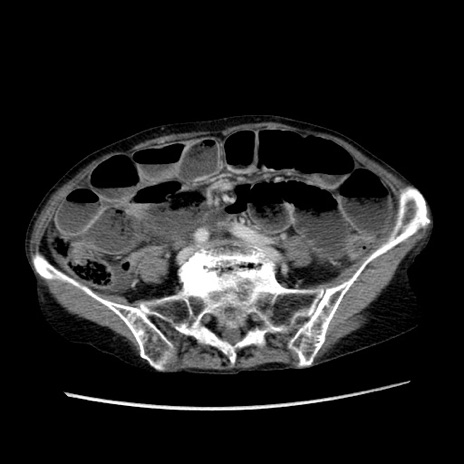

症例25(横断像)

【症例】80歳代女性

【主訴】胸のつかえ感

【現病歴】約9時間前に食後から胸のつかえた感じあり、嘔吐あり、来院。

【既往歴】胃癌(全摘)、胆摘、虫垂炎

【身体所見】心窩部に圧痛あり、反跳痛なし。

【データ】WBC 5700、CRP 0.05